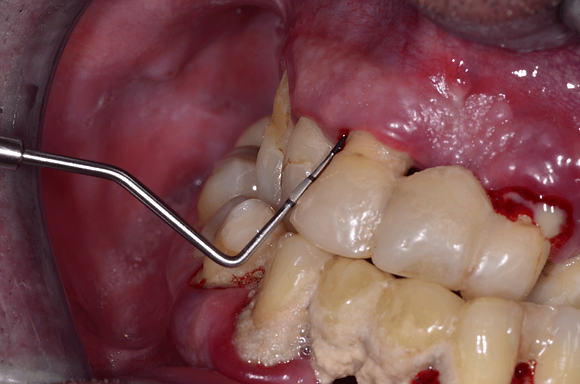

W badaniu podczas zapalenia dziąseł obserwuje się zaczerwienienie, obrzęk dziąseł oraz krwawienie występujące podczas szczotkowania, nitkowania zębów lub delikatnego badania sondą peridontologiczną.

Dlatego sonda periodontologiczna to najważniejszy instrument na tacy zabiegowej higienistki.

Służy do oceny:

- głębokości kieszeni przyzębnych,

- grubości dziąsła,

- pomiaru recesji dziąsłowej, utraty przyczepu,

- badania kamienia poddziąsłowego

- oraz obliczania parametrów zapalenia dziąseł – wskaźników.